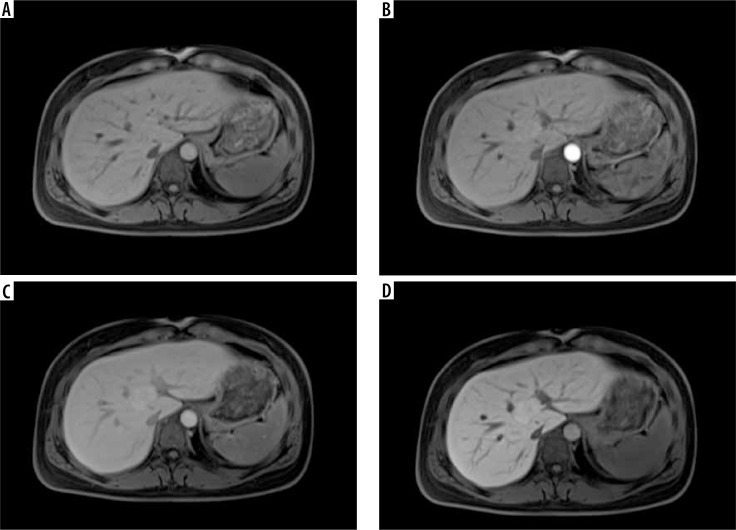

Abstract Image